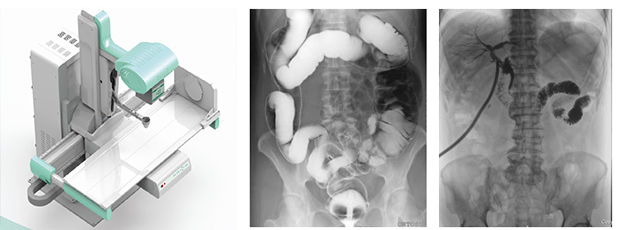

x線數(shù)字胃腸機(jī)

x線數(shù)字胃腸機(jī)主要用來進(jìn)行咽喉部、食道、胃、十二指腸、空回腸及結(jié)腸各種疾病的造影診斷。這款醫(yī)用設(shè)備由高壓發(fā)生器、球管、影像增強(qiáng)器、電動(dòng)檢查床曝光控制臺(tái)和數(shù)字處理工作站組成。

x線數(shù)字胃腸機(jī)的實(shí)質(zhì)其實(shí)是多功能數(shù)字成像系統(tǒng),采用影響增強(qiáng)器把X光轉(zhuǎn)化為可見光,由電荷耦合器將可見光轉(zhuǎn)化為視頻信號(hào),轉(zhuǎn)監(jiān)視器顯示,是一種新的成像方式。流程簡單,操作方便,既達(dá)到診斷目的又減輕病人痛楚。主要特點(diǎn)是準(zhǔn)確、高效、全能。

采用的平板探測器成像性能優(yōu)異,像素148微米,灰階16bits,圖像清晰準(zhǔn)確,為臨床診斷提供了準(zhǔn)確的依據(jù)。

超大視野的x線數(shù)字胃腸機(jī)

17”×17”(43cm×43cm)碘化銫非晶硅動(dòng)態(tài)平板探測器。超大視野全腹覆蓋。記錄一個(gè)成年人的吞咽過程無須移動(dòng)平板,不產(chǎn)生偽影。對(duì)于一些身材高大的患者,無論是頭端,還是下肢,均可全部覆蓋,拍攝無遺漏。

一機(jī)多能,既可以完成消化道造影、靜脈腎盂造影等各種造影檢查,又可以完成DR圖像的拍攝。保證無論靜態(tài)或動(dòng)態(tài)圖像都完美無缺 。